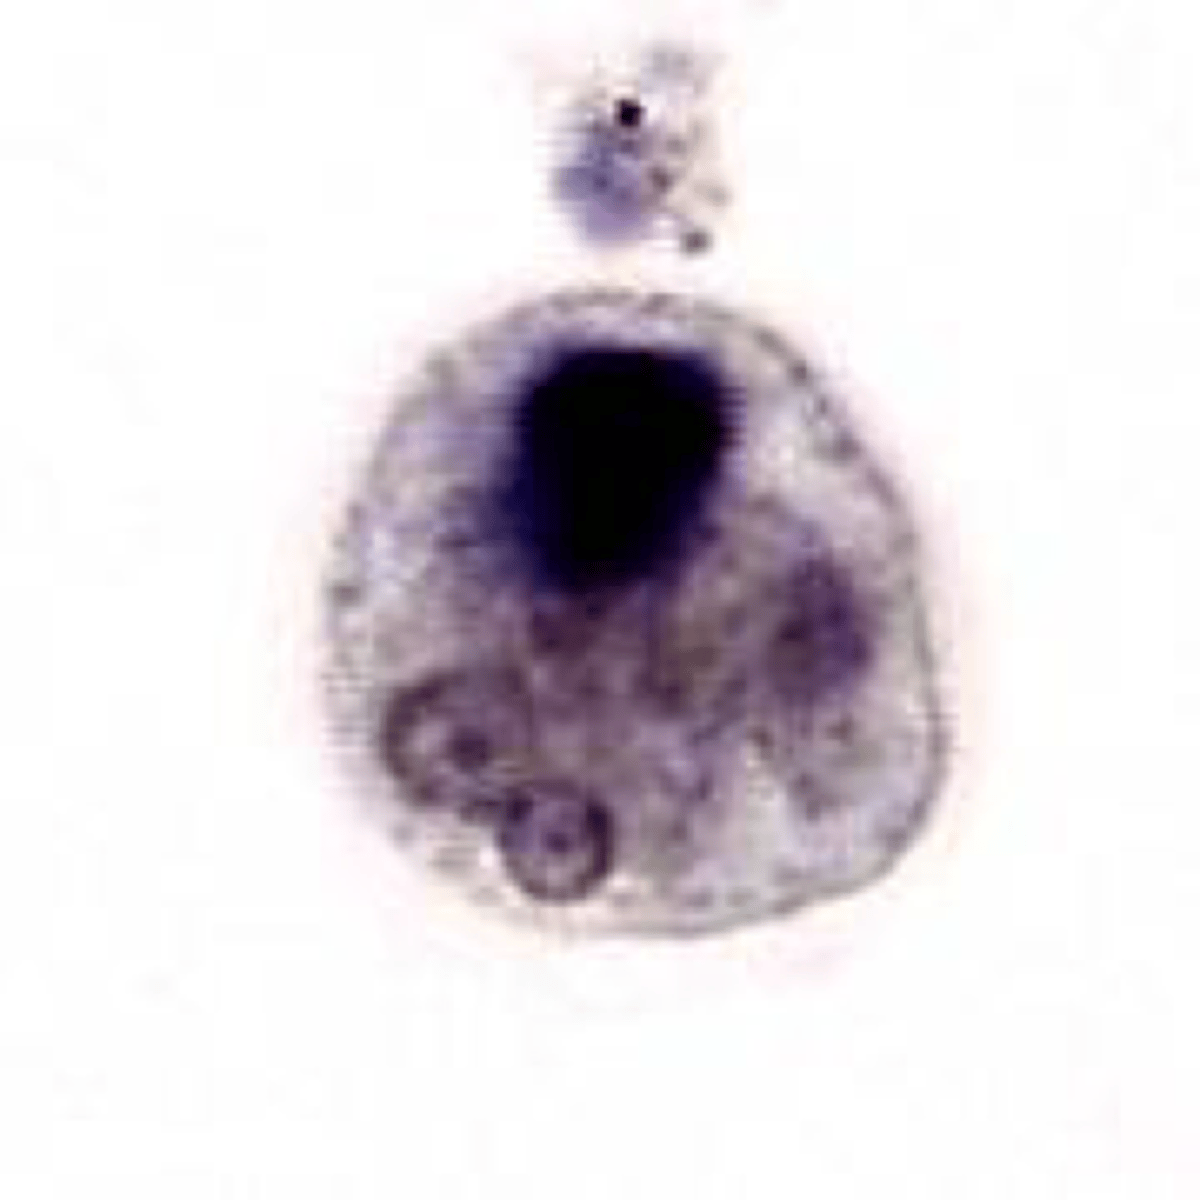

Entamoeba coli - Trophozoite

Name the stage and species.

NOTE: Endosome eccentric and larger granules in the ring of peripheral chromatin. Also note how many more medium cytoplasmic vacuoles are present.

<p>Name the stage and species.</p><p>NOTE: Endosome eccentric and larger granules in the ring of peripheral chromatin. Also note how many more medium cytoplasmic vacuoles are present.</p>